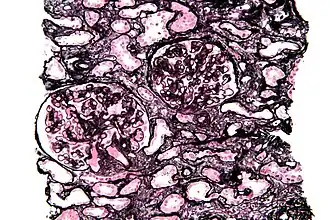

La tinción de Jones muestra las proyecciones membranoides prominentes (spikes) de la membrana basal glomerular causadas por depósitos subepiteliales que se observan en la nefropatía membranosa .